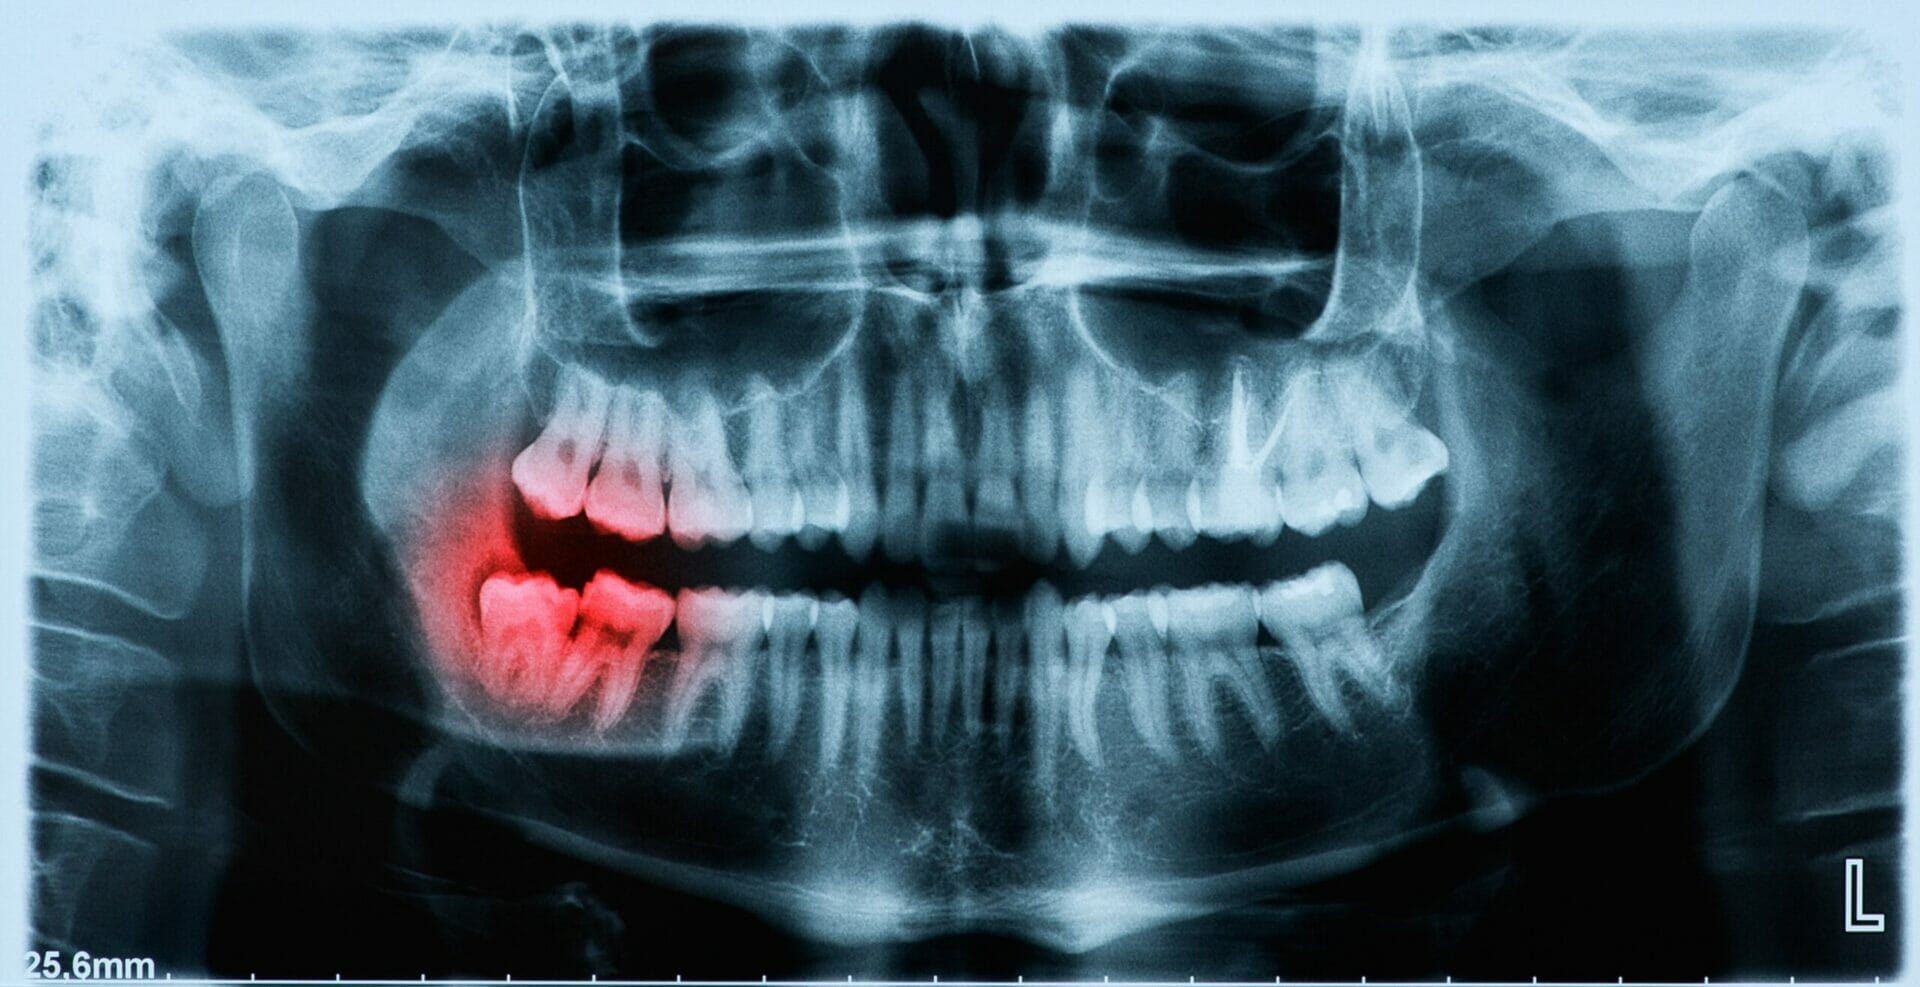

When I recommend wisdom tooth removal for a teenager, parents often ask "who does wisdom tooth removal near me?". At our clinic, we remove the majority of impacted wisdom teeth under local anesthetic, with or without an additional sedative such as laughing gas (nitrous oxide). In some cases, a referral for extraction with the local Oral Surgeon is made. Reasons for this include:

Oral Surgery & Tooth Removal